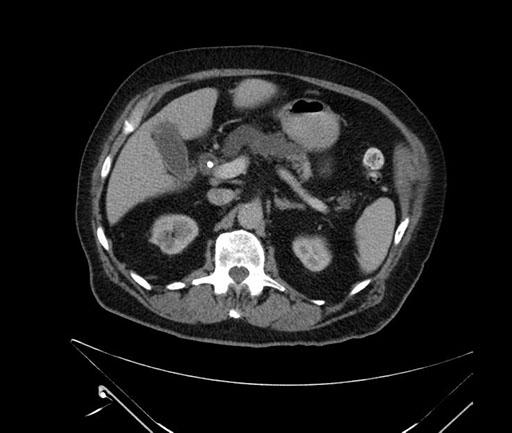

Whipple (pancreaticoduodenectomy) [case 7]

Axial - stented

Imaging analysis

Based on your CT findings, which issue(s) would give reason for "planned slowing down moment(s)" in this case?

Considering a standard Whipple procedure, what step(s) of the operation would you do differently in this case?